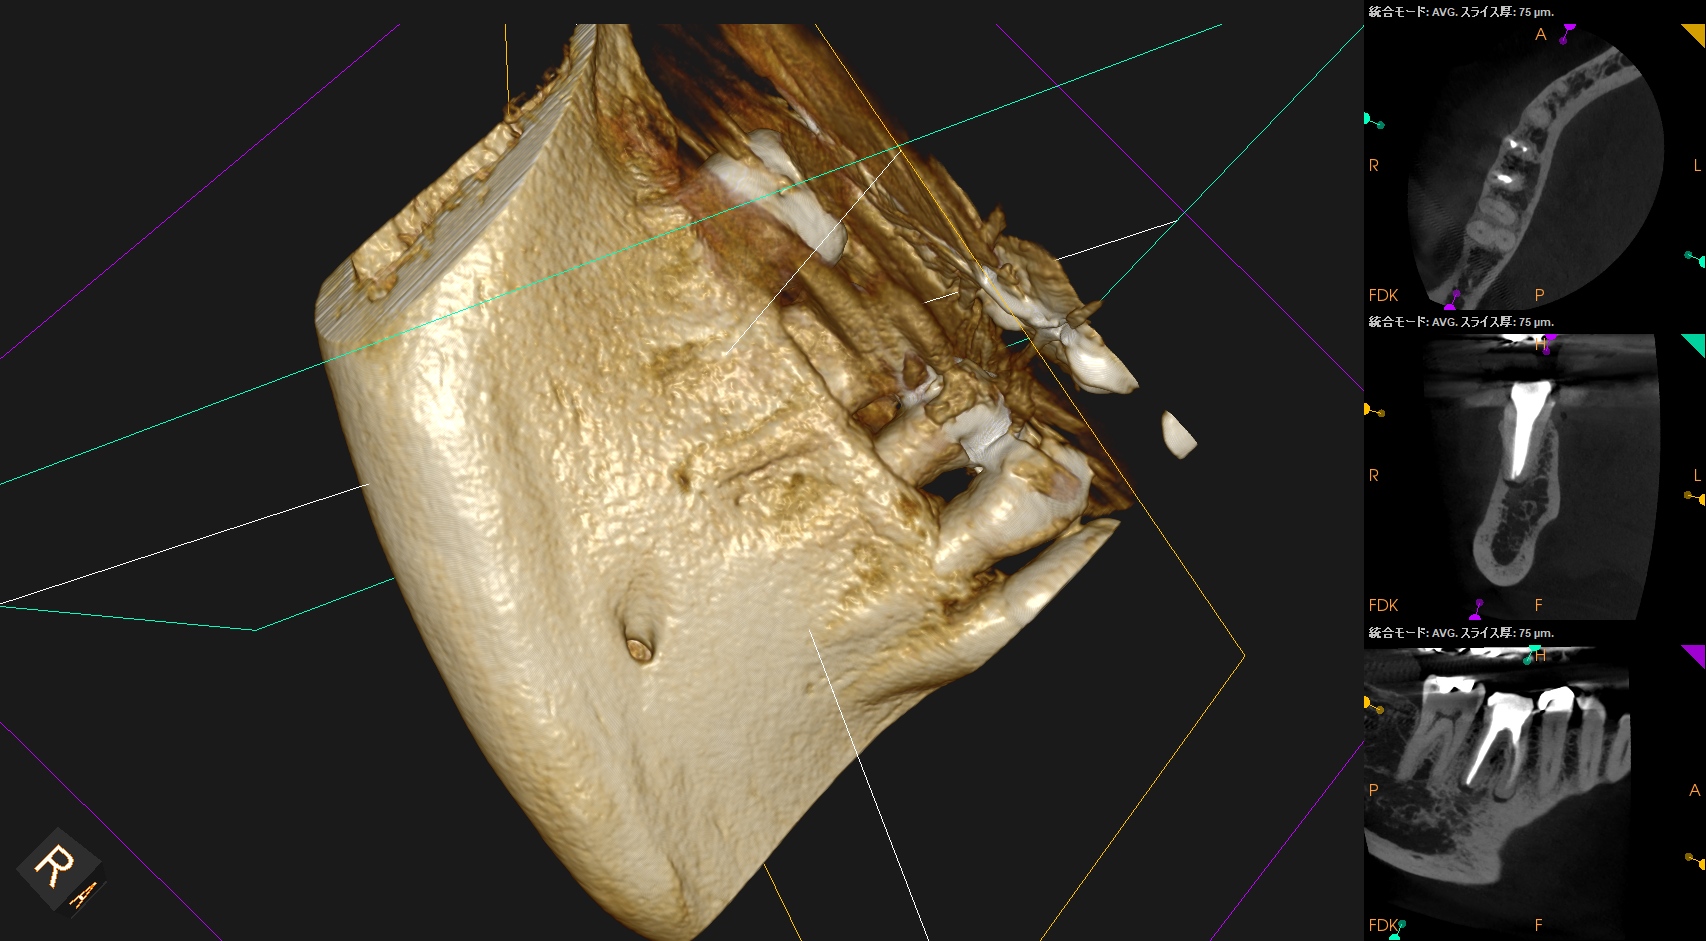

CBCT(2025.10.15)

#30 MB

#30 ML

#30 D